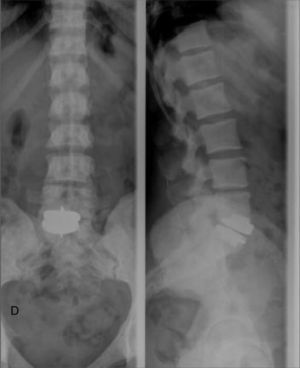

En un control radiográfico rutinario de la columna lumbar (fig. 1), se observan numerosos focos pequeños, bien definidos, homogéneos, circulares, de mayor densidad ósea, en los cuerpos vertebrales, a lo largo de todo el esqueleto axial, por lo que se amplía estudio con radiografía de pelvis AP (fig. 2) y TAC de pelvis y cuerpo vertebral lumbar (figs. 3 y 4), que mostraban lesiones radiodensas redondeadas u ovales en la cabeza y el cuello femorales y en regiones pertrocantéreas, con presencia de pequeñas áreas de densidad aumentada en la pelvis y en los cuerpos vertebrales que indicaban como primer diagnóstico osteopoiquilia. No se observaban componente de partes blandas, ni áreas de rotura de la cortical, ni presencia de reacciones periósticas de características agresivas.